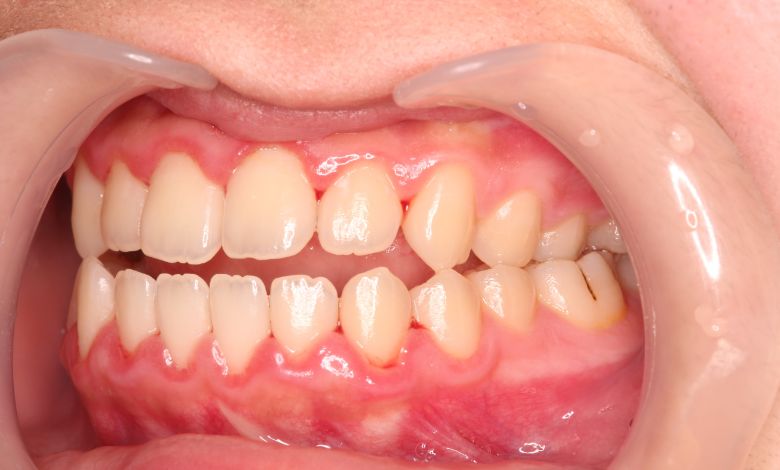

上下顎ともに犬歯が唇側に大きく突出しており、歯列弓が狭小なため、

他院では上下左右4本の便宜抜歯を前提とした矯正治療を提案されていました。

上顎には左右の犬歯が著しく唇側に偏位している

上下ともに歯並びが乱れており、噛み合わせにも大きな不調和が見られる

精密検査の結果、当院では抜歯を行わず、歯列弓の拡大によってスペースを確保し、非抜歯での矯正治療を選択しました。歯列の叢生(ガタガタ)は解消され、機能的かつ審美的に優れた咬合が得られました。